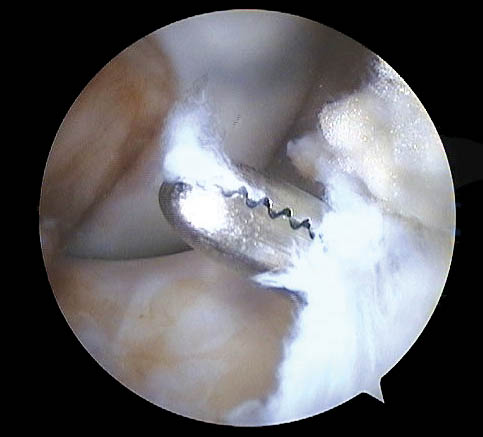

Respecto a su morfología usamos la clasificación de Lage et al.28 (Figs. 9, 10 y 11) que se distribuyeron de la siguiente manera:

Figura 9: Lesión labral fibrilar.

Figura 10: Lesión labral por mecanismo Pincer.

Figura 11.